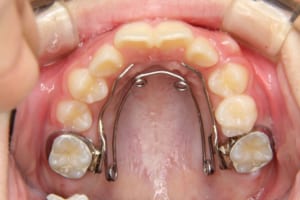

治療中

| 使用した装置 | 子どもの矯正治療(前期治療) 緩徐拡大装置 マルチブラケット装置 大人の矯正治療(後期治療/成人矯正治療) マルチブラケット装置 デーモンブラケット シルバーワイヤー 歯科矯正用アンカースクリュー(2本) ホールディングアーチ トランスパラタルアーチ |